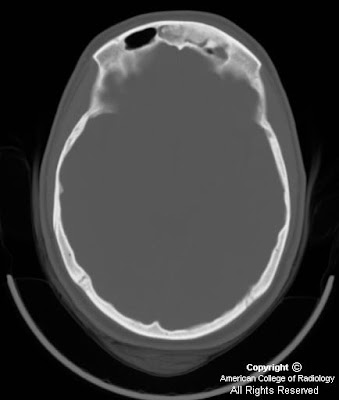

Findings

Imaging characteristics of the tumors in schwannomatosis are the same as those of sporadic schwannomas. Iso/hypointensity on T1 weighted images, hyperintensity (secondary to cystic change, and occasionally hemorrhage) on T2 weighted and STIR images and avid contrast enhancement are typical findings.

Dedicated imaging of the internal auditory canals and the brain should be pursued to help clarify the diagnosis. Follow up imaging is also indicated, especially if the diagnosis is not definitive, as malignant degeneration of an NF2 lesion would manifest as rapid increase in size of a mass.